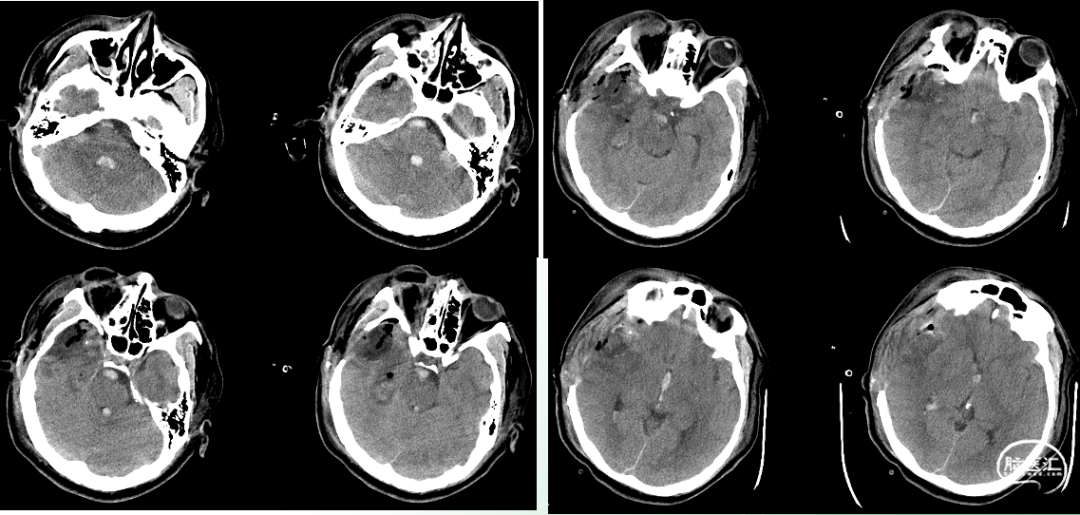

术后即时影像

血管造影影像